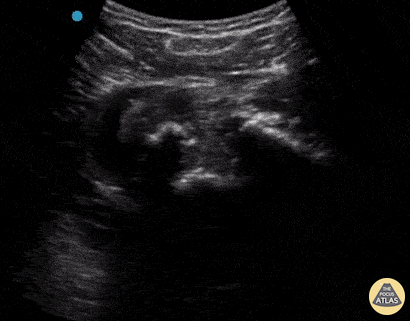

A 30-year-old male presented to the emergency department with an inferior shoulder dislocation (luxatio erecta). Studies have shown that ultrasound has a very high sensitivity and specificity nearing 100% each (Secko 2020) in identification of the same. On ultrasound, the humeral head is shown dislocated anterior to the glenoid fossa, similar to typical anterior shoulder dislocations. This patient's shoulder was reduced with simple traction/countertraction under procedural sedation without any complications. Mark Zhang Secko MA, Reardon L, Gottlieb M, et al. Musculoskeletal ultrasonography to diagnose dislocated shoulders: a prospective cohort. Annals of Emergency Medicine. 2020;76(2):119-128.